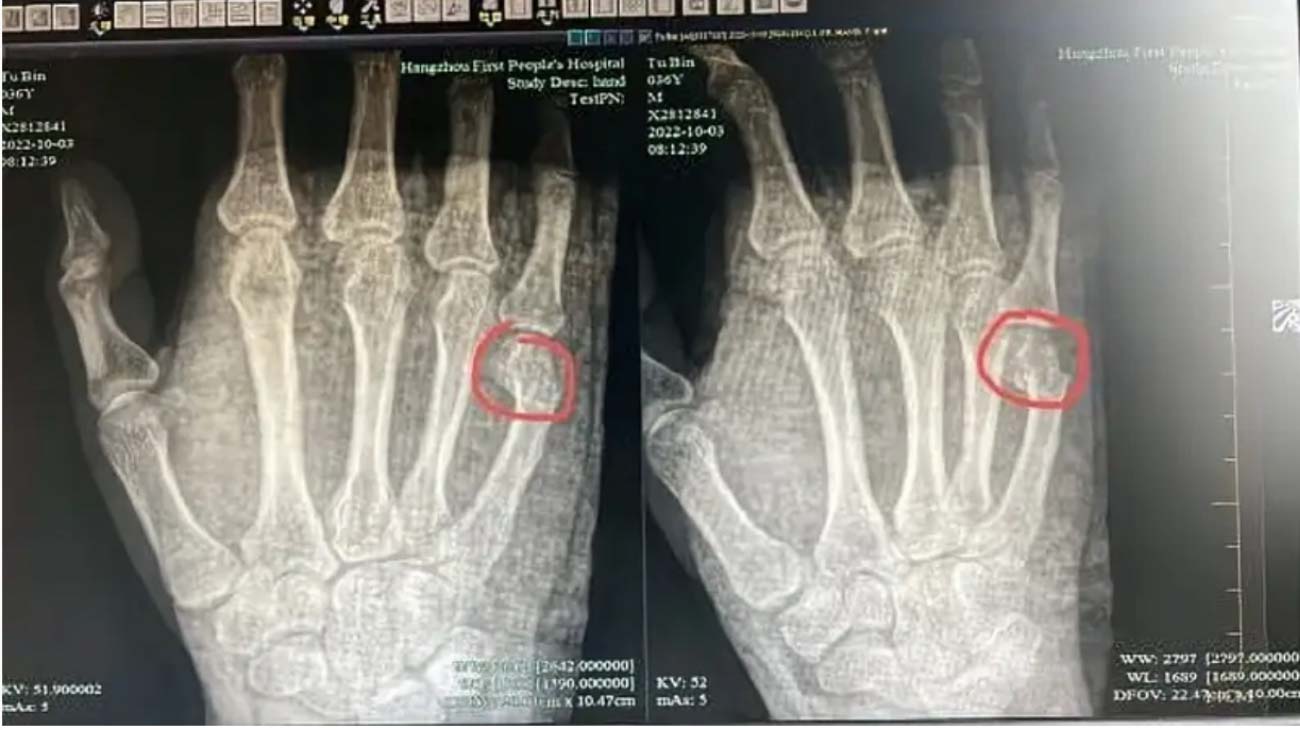

▲吳爸爸一拳搥到自己骨折。(圖/百度)

最後吳爸爸忍不住吼了兒子幾聲,沒想到兒子也是個拗脾氣,竟直接把筆給放在桌子上,也不解題了!吳爸爸忍無可忍,直接一拳砸在了書桌上!沒想到這一拳揮出之後手掌劇痛,原來是他的手掌第五指指股遠端骨折,斷處明顯位移,甚至還需要住院治療。